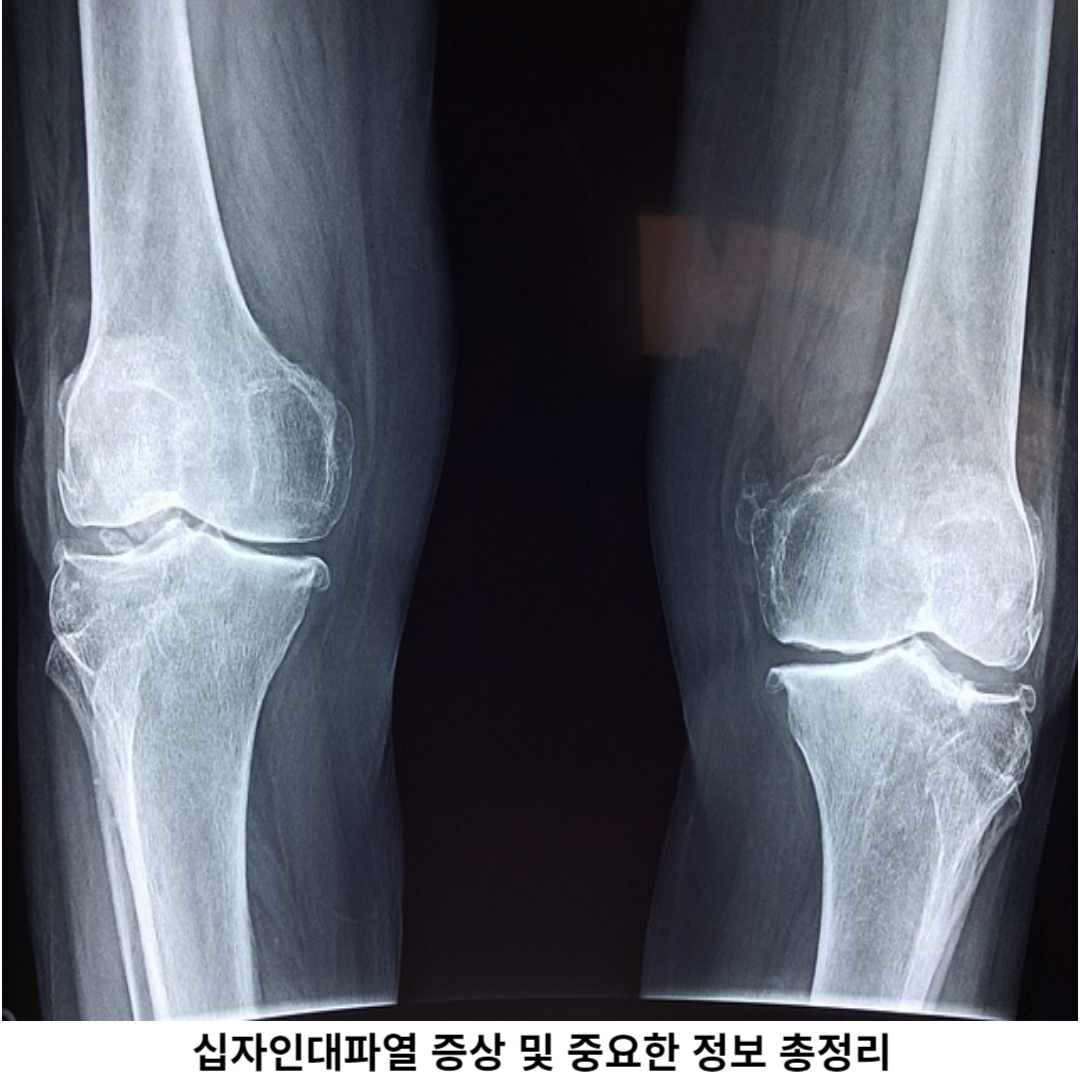

십자인대파열은 하지를 구성하는 인대 중 하나인 십자인대의 파열을 의미합니다. 이 십자인대는 높은 인장력과 스트레스를 견디지 못할 때 파열될 수 있는데, 이는 주로 강한 외력이나 무리한 움직임으로 인해 발생합니다.

십자인대파열은 다리를 지탱하는 역할을 하는 십자인대가 손상되면 발생합니다. 이로 인해 통증, 부종, 불안정한 느낌 등이 초래될 수 있습니다. 이러한 손상이 발생하면 종종 '무릎이 흔들린다'는 느낌을 주며, 무릎이 불안정해질 수 있습니다.

의사는 클리니컬 검사와 영상 검사를 통해 정확한 진단을 내릴 수 있습니다. 진단 후, 수술이 필요한 경우, 수술 전후에 물리치료나 재활치료가 필요할 수 있습니다. 이러한 치료를 통해 환자는 빠른 회복을 이룰 수 있습니다.